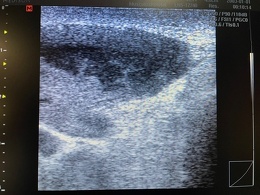

デイサービスご利用者様の膝のエコー写真です。

機能訓練時に膝の疼痛を訴えられたため、エコーにて観察。

膝外側に関節水腫、内側に脂肪種様物質、膝窩(膝の裏側)にBaker嚢腫を確認しました。

1週間後には膝外側の水腫は消失しておりましたが、脂肪種、Baker嚢腫は変わらないので医療機関の受診をお勧めしました。